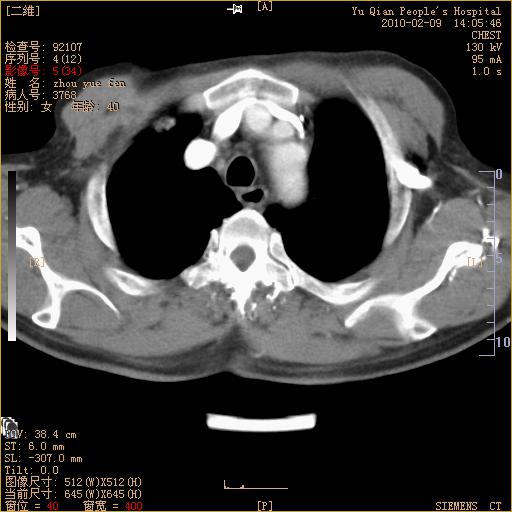

男性,73岁,咳嗽咳血数天,诊为肺ca伴左肺下叶后段阻塞性炎症、肺不张妥否?

左下肺中央型肺癌伴结段形肺不张,左侧胸腔积液,纵隔内见部分增大淋巴结(反应性增生或转移)

左下基底干支气管明显变窄。

左肺下叶基底段支气管狭窄,左肺门增大,左肺下叶团片状病灶。中心型肺癌伴柱塞性炎症可能大,建议支气管镜检查。

左下肺中央型肺癌伴节段性肺不张,左侧胸腔积液,纵隔内见肿大淋巴结

左下基底段支气管变窄。建议进一步纤支镜检查。

1、左肺下叶后基地段肺癌伴阻塞性炎症,左下肺门淋巴结转移。2、左侧胸腔积液。